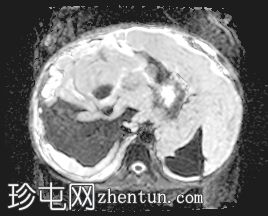

轴向

T2

升结肠壁增厚,尤其前壁,形成肿块,T2信号高,提示其为黏液性肿块。肿块无扩散受限,增强扫描后几乎无强化。

腹腔内可见大量T2信号高、T1信号低至中等的包裹性积液,与腹膜凹陷相符,并导致内脏表面(尤其是肝脏和脾脏)呈扇贝状。这些表现是腹膜假黏液瘤的特征性表现,可能由黏液性肿瘤播散引起。